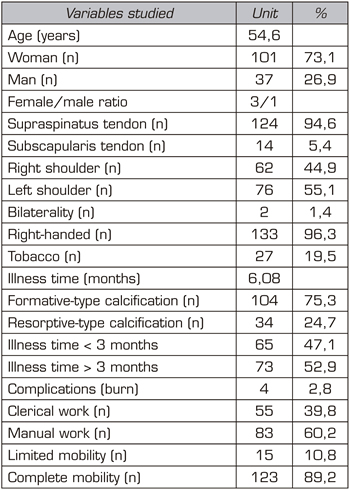

The age of the patients in the sample was 54.6 years (n = 1 38). The most frequent sex was female (73.1%; n = 101), with a 3/1 female/male ratio (Table I). Among the history associated with CT, smoking (19.5%; n = 27) and diabetes (7.2%; n = 10) stood out (Table I).

The most affected tendon was the supraspinatus tendon (94.6%; n = 124), followed by the subscapularis tendon (5.4%; n = 14) (Table I). Regarding laterality, the most frequently affected shoulder was the left one (55.1%; n = 76), followed by the right (44.9%; n = 62). Only two patients had bilateral CT (1.4%; n = 2) (Table I). Regarding dominance, most of the patients were right-handed (96.3%; n = 133).

Table I. Evaluation of the main variables studied (n = 138)

The mean illness time in this study was 6.08 months. Acute-subacute pain (less than 3 months) was less frequent (47.1%; n = 65) than chronic pain (more than 3 months) (52.9%; n = 73) (Table I).

The most frequent radiological type was formative (75.3%; n = 104), followed by resorptive (24.7%; n = 34). The average number of sessions applied was 20.5. A total of 2.8% of the patients (n = 4) stopped the treatment due to intolerance, erythema and/or burn; therefore, they completed the treatment with ultrasound or short wave according to tolerance (for pain management). With regard to occupation, 39.8% (n = 55) were clerical work, while 60.2% (n = 83) conducted a manual work (Table I).

Regarding mobility, 10.8% (n = 15) of the patients presented functional limitation in the affected shoulder (Table I).